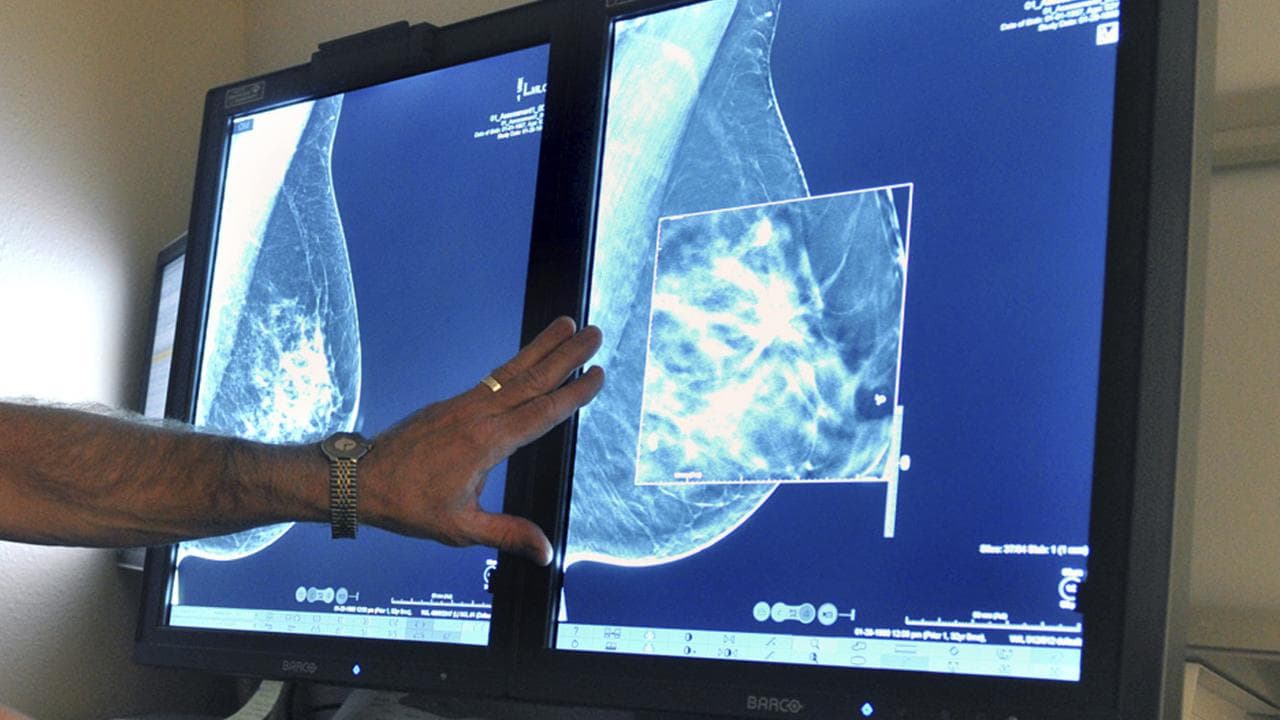

She then booked in to see her GP who referred her for an ultrasound at the Geelong breast clinic which was followed by multiple diagnostic tests.

Australia's BreastScreen program is free for women over 40 and women over 50 are invited for a mammogram every two years.

There is no evidence to support routinely screening women under 40, unless they are at high risk of developing breast cancer due to genetic mutations, National Breast Cancer Foundation chair in cancer prevention Nehmat Houssami says.

"A key message for women, including younger women, but relevant to all women even if they have recently screened, is if you notice a change in your breast ... then please see your family doctor and talk to them about being referred for testing," she says.

"Medicare covers some of the cost of these tests but unless the service bulk bills there will be out-of-pocket expenses," Professor Houssami says.